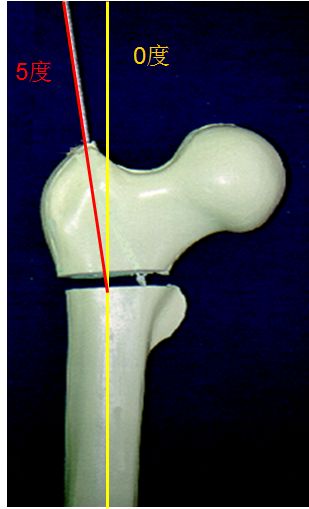

进针点